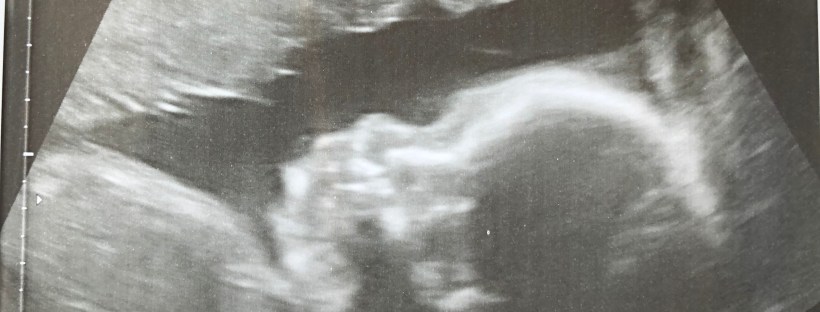

Losing LBR 3.0 – Dealing with Miscarriage

This draft has been sitting in my folder since April 3. Almost 3 months have gone by and I have opened and closed it more times than I could count. It's been written in my planner on my running 'to do' list ever since I started it. Still, I haven't been able to bring myself … Continue reading Losing LBR 3.0 – Dealing with Miscarriage